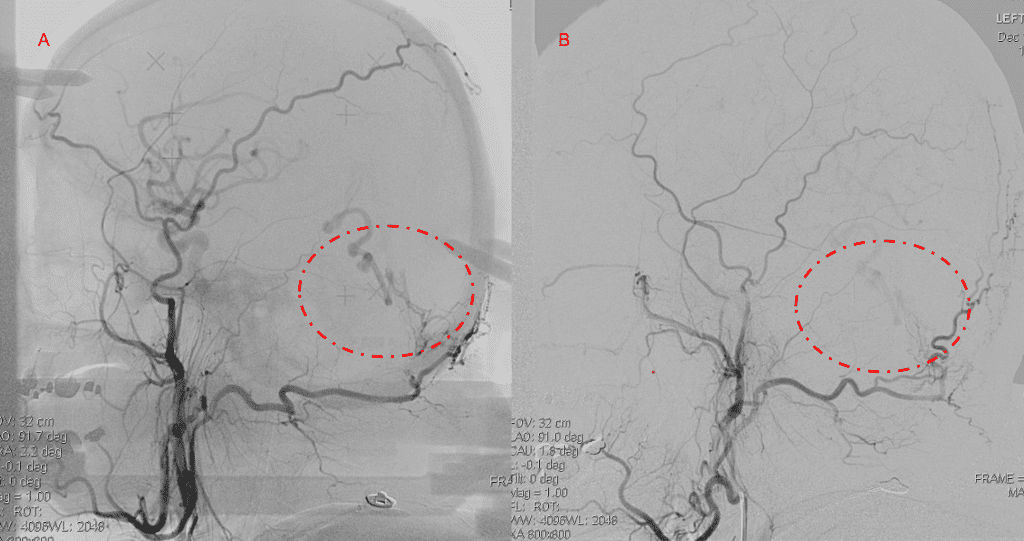

A 55-year-old woman presented with acute onset of severe headache, and possible witnessed seizure. Imaging confirmed intraventricular hemorrhage primarily focused within the fourth ventricle with diffuse subarachnoid hemorrhage within the posterior fossa and along the tentorium as observed on non-contrast CT and MRI of the Brain (Figure 1).

Figure 1. A and B) Non-Contrast CT Axial and Coronal demonstrate large, ruptured Varix/Aneurysm along the Incisura of the posterior fossa which appears to have mixed hemorrhagic components and enhancement on MRI T2 and post contrast imaging (C and D).